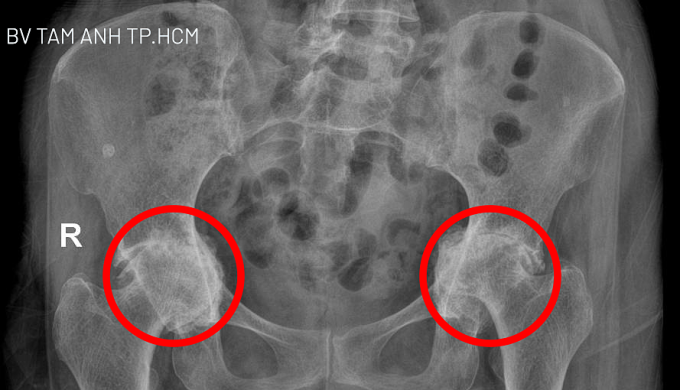

Trước đó, chị San Samphors điều trị bằng thuốc ở bệnh viện tại Campuchia, Thái Lan không khỏi, gần đây đau nặng hơn. Kết quả chụp X-quang tại Bệnh viện Đa khoa Tâm Anh TP HCM cho thấy sụn ở hai bên khớp gối của người bệnh bị mài mòn hoàn toàn và tiêu biến. Khớp háng hai chân thoái hóa nặng, chỏm xương đùi lệch khỏi vị trí bình thường, chui vào trong ổ bụng. Bác sĩ Khoa nhận định đây là trường hợp rất nặng, phẫu thuật là phương pháp duy nhất giải phóng người bệnh khỏi đau đớn và khôi phục khả năng vận động.

Kết quả chụp X-quang cho thấy khớp háng hai bên phá vỡ khung chậu và đang dần chui vào ổ bụng. Ảnh: Bệnh viện Đa khoa Tâm Anh

Kết quả chụp X-quang cho thấy khớp háng hai bên phá vỡ khung chậu và đang dần "chui" vào ổ bụng. Ảnh: Bệnh viện Đa khoa Tâm Anh